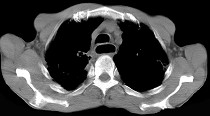

- 单项选择题女性患者,67岁进行性吞咽困难半年, X线及CT检查如图,应诊断为 ( )

A、食管癌

B、食管憩室

C、食管炎

D、食管良性狭窄

E、食管静脉曲张